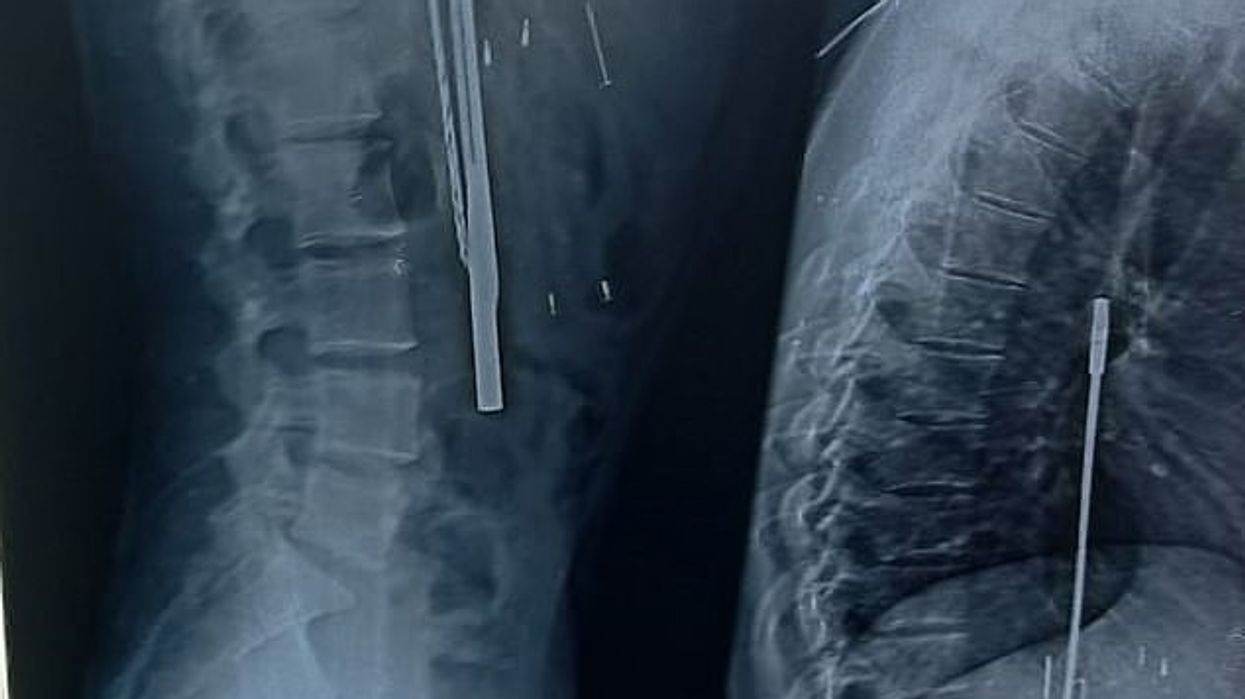

E ëma e tij, Kusma Thakur, u tha mjekëve se djali i saj "hante gjithçka që i dilte përpara", dhe kështu ata u detyruan t'i bëjnë rëntgenografinë për të konstatuar se për çfarë bëhej fjalë.

Mirëpo, mbetën të habitur kur në bark i gjetën thika, kaçavidë, bisturi dhe objekte tjera. E dy ditë pas intervenimit kirurgjik, mjekët kanë publikuar listën e plotë të objekteve që i kanë gjetur në barkun e fermerit indian që tani po rimerr veten në spitalin e psikiatrisë. /Telegrafi/